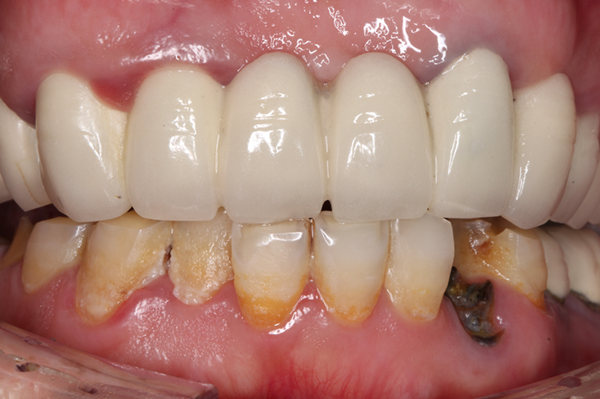

种牙成功后的郄女士

种植成功后的牙齿

手术全程就是在打麻药的时候有点痛,就像蚊子咬一样,而且手术全程工作人员都很贴心,每一步都告诉我接下来要做什么,我觉得把牙齿问题交给麦芽,我很放心!